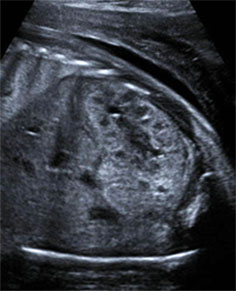

UCSF‘s ultrasound subspecialty utilizes state-of-the-art, high-resolution ultrasound machines equipped with 2D, 3D and 4D capability along with color and duplex doppler imaging to create real-time sonograms of patients.